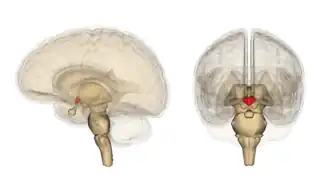

Гипотала́мус[1] (лат. hypothalamus, от др.-греч. ὑπό ‘под’ и θάλαμος ‘комната, камера, отсек, таламус’) — небольшая область в промежуточном мозге, включающая в себя большое число групп клеток (свыше 30 ядер)[2], которые регулируют нейроэндокринную деятельность мозга и гомеостаз организма. Гипоталамус связан нервными путями практически со всеми отделами центральной нервной системы, включая кору, гиппокамп, миндалину, мозжечок, ствол мозга и спинной мозг. Вместе с гипофизом гипоталамус образует гипоталамо-гипофизарную систему, в которой гипоталамус управляет выделением гормонов гипофиза и является центральным связующим звеном между нервной и эндокринной системами. Он выделяет гормоны и нейропептиды и регулирует такие функции, как ощущение голода и жажды, терморегуляция организма, половое поведение, сон и бодрствование (циркадные ритмы). Исследования последних лет показывают, что гипоталамус играет важную роль и в регуляции высших функций, таких как память и эмоциональное состояние, и тем самым участвует в формировании различных аспектов поведения.

Гипоталамус является частью промежуточного мозга. Он образует основание и стенки нижней части третьего желудочка. Название своё он получил от греч. гипо- (под, внизу) и таламос (чертог, спальня), так как он располагается под таламусом. Гипоталамус отделён от таламуса гипоталамической бороздой (лат. sulcus hypothalamicus). Анатомические границы гипоталамуса определены недостаточно чётко, что связано с тем, что некоторые группы клеток заходят в соседние области, а также с некоторой неопределённостью в терминологии[3]. Считается, что спереди (рострально) гипоталамус ограничен терминальной пластинкой (лат. lamina terminalis), а его задняя (каудальная) граница — воображаемая линия от задней комиссуры (лат. commissura posterior) до каудальной поверхности сосцевидных тел. Дорсолатерально гипоталамус доходит до медиального края мозолистого тела[4].

В нижней части гипоталамуса выделяются такие структуры, как сосцевидные тела (лат. corpus mamillare), серый бугор (лат. tuber cinereum) и воронка (лат. infundibulum). Воронка отходит от серого бугра, средняя часть воронки приподнята и называется срединным возвышением (лат. eminentia mediana), которое в некоторых классификациях относят к серому бугру, а в некоторых — к нейрогипофизу[5]. Срединное возвышение содержит кровеносные сосуды, переносящие выделяемые гипоталамусом вещества в гипофиз. Нижняя часть воронки переходит в ножку гипофиза.